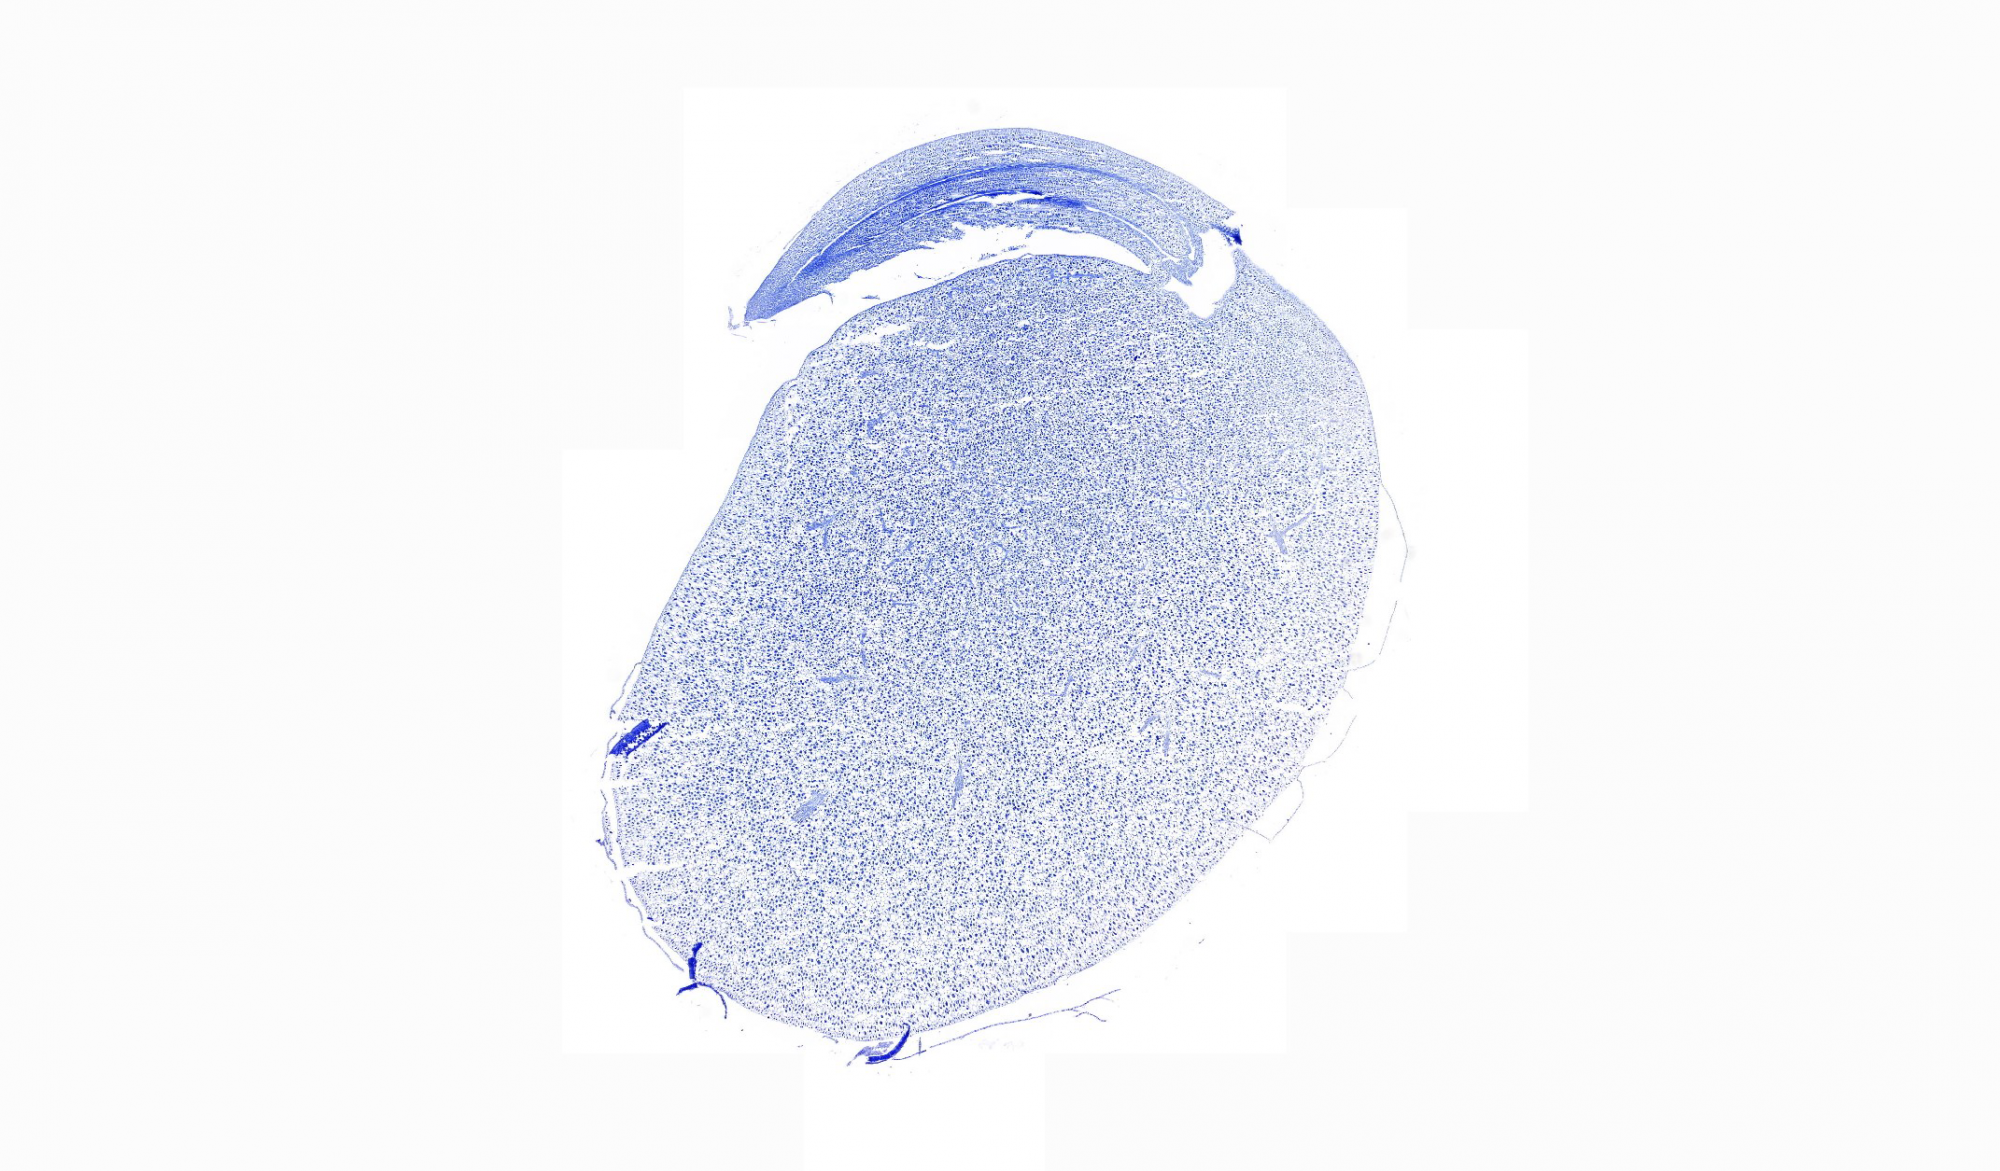

病理平臺(tái)可承接:石蠟切片,切片掃描,熒光掃描,HE染色,各種特殊染色,如:Masson、油紅O、PAS、番紅O、ALP、TRAP、甲苯胺藍(lán)以及免疫組化/熒光、原位雜交等,3D HISTECH滿足對(duì)結(jié)果高質(zhì)量,高標(biāo)準(zhǔn),周期快的實(shí)驗(yàn)外包需求,并提供染色培訓(xùn)服務(wù),分線上視頻,線下實(shí)操帶教兩種培訓(xùn)方案。

案例展示

組織染色實(shí)驗(yàn)室